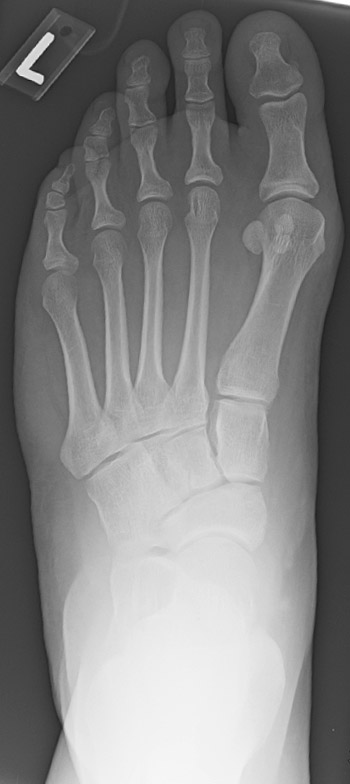

A study by Kamanii and colleagues looked at 20 people who were diagnosed with joint hypermobility syndrome according to Beighton and Bulbena score models.5,6 Comparing these people to 20 healthy controls, the researchers obtained weightbearing anteriorposterior (AP) and lateral radiographs, and assessed 11 angles. The authors found a statistically significant difference in calcaneal pitch and tarsometatarsal angles on lateral radiographs, and the first metatarsophalangeal joint (MPJ) angles on AP radiographs. From their data, the study authors suggested that people with hypermobility were predisposed to having a pes planus foot type and HAV deformities.

King and Toolan compared 15 healthy people without HAV to 25 individuals who failed conservative treatment for HAV.7 The investigators compared clinical evaluations between the two groups for hypermobility. They determined hypermobility using two methods. They assessed dorsiflexion of the first ray relative to the lesser rays with manual dorsiflexion force and subsequently assessed overloading of the second ray as determined by a plantar hyperkeratotic lesion. Researchers evaluated weightbearing AP and lateral radiographs for both groups to compare the distal metatarsal articular angle, intermetatarsal angle, MPJ angle, talonavicular coverage and the talo-first metatarsal angle. On the lateral radiographs, the study authors assessed the lateral MPJ angle, the talo-first metatarsal angle and Meary’s angle.

The authors also evaluated two new parameters for measuring hypermobility on the lateral radiographs.7 The first was the perpendicular distance between the plantar aspect of the medial cuneiform and the plantar aspect of the first metatarsal. The second technique was to measure the angle formed by the medial cuneiform and first metatarsal articular surface, extending from the superior to the inferior aspect of the joint. All the patients with HAV had clinical signs of hypermobility. In comparing patients with HAV to healthy people, the study findings revealed statistically significant differences in the distal metatarsal articular angle, the intermetatarsal angle, the MPJ angle, talonavicular coverage, the lateral talo-first metatarsal angle, the dorsal translation of the first metatarsal, the medial cuneiform/first metatarsal articular angle, and the lateral MPJ angle.

King and Toolan concluded that there was a correlation between radiographic and clinical testing for hypermobility as well as an indication for lateral imaging in determining hypermobility.7 They suggest that measurement of the dorsal translation of the first metatarsal and the medial cuneiform/first metatarsal articular angle could represent “quantifiable radiographic measures” for defining hypermobility.

From the high rate of recurrence, we can see that correction of HAV in the presence of hypermobility is not as simple as constraining the first metatarsal in space. In fact, the current thinking about the HAV deformity may not consider hypermobility as an important indicator for treatment. Dayton and colleagues state that osteotomies are mainly treating only the reduction of the intermetatarsal angle.15 They suggest that the deformity correction should take place at the center of rotation of angulation (CORA) as described by Paley and coworkers.15,16 The area of correction then would exist at the metatarsal cuneiform joint and thereby not create a secondary CORA with an osteotomy.15 Dayton and colleagues also address the frontal plane or “third plane” of the bunion deformity by derotating the first metatarsal in the frontal plane with the first tarsometatarsal arthrodesis.17 The frontal plane of deformity is visible on the sesamoidal axial radiographs as a valgus rotation of the metatarsal.

Most recently, valgus rotation of the metatarsal has become a critical element in our understanding of the cause of HAV and the role of hypermobility. Plain radiographs that show an elevated tibial sesamoid position imply that the metatarsal has migrated laterally, resulting in a bowstringing effect of the flexor tendon. However, if one considers the sesamoid position on a sesamoid axial view, it is apparent that the sesamoid remains within the sesamoid grooves in contact with the metatarsal head. Instead, the entire metatarsal rotates into a valgus position.

This brings an entirely new perspective to the term hypermobility. The rotation of the metatarsal itself gives the impression of lateral deviation of the sesamoids on the AP radiograph.15 Therefore, with triplanar correction of the bunion deformity at the metatarsal cuneiform joint, one can achieve the necessary correction at the center of rotation of angulation. By addressing the valgus rotation of the metatarsal in addition to the increased metatarsal angle and the decreased metatarsal declination angle, the metatarsal head appears to move into a more correct position. In many cases, this can eliminate the need for additional soft tissue balancing such as adductor hallucis tendon releases and lateral collateral fibular sesamoid ligament releases.15,17